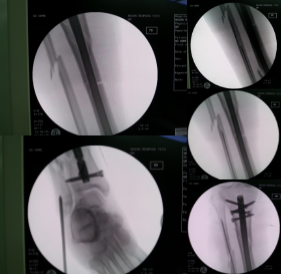

最终选择髌骨上入路髓内钉固定。

1、使用牵开器维持骨折端基本的对位,对线。省时,省力不吃射线。

2、近端通过阻挡钉技术辅助骨折断端复位。

3、使用特殊的「 锁定型髓内钉 」远端即便只锁 2 枚锁钉依然稳定。

腓骨采用弹性髓内钉固定

术后复查